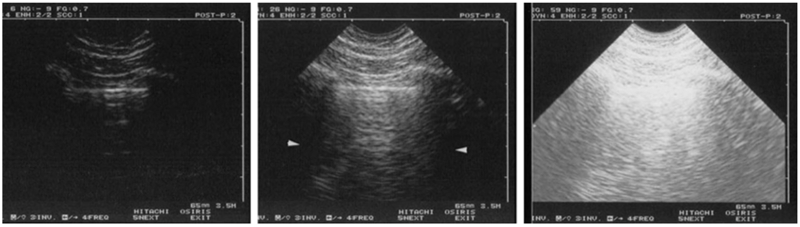

Optimal control of gain is obtained with experience. At the lung, this step can be standardized. Radiologists have long defined the best gain as giving a gray (healthy) liver and a black (healthy) gallbladder content. We can do the same with lung ultrasound: the best gain gives black shadows of ribs, grey parietal tissues, and white pleural line (Fig. 3). In the units we use, the proximal, distal, and global gains can be adjusted. That said, we modify only the global gain, from time to time, and quite never the proximal and distal gains.

Fig. 3 Standardized gain for lung ultrasound. Longitudinal scan of the lung. Left: The gain is too low. Details are lost. Middle: The gain is optimal, clearly showing the pleural line. Right: The gain is too high: superficial areas are saturated